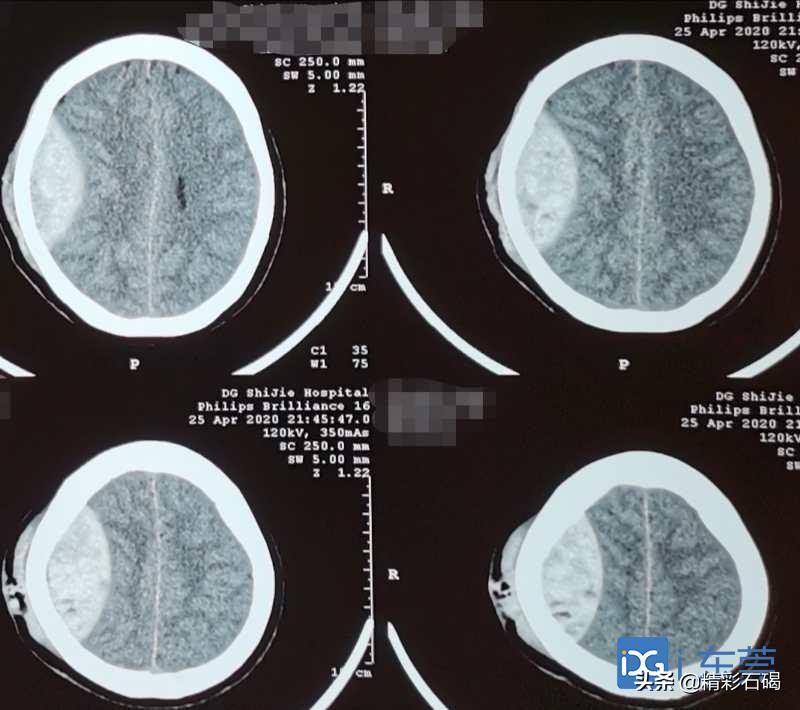

术前

术后

祝阿姨在被送进石碣医院急诊科时,医护人员迅速对祝阿姨进行初步检查处理,在完善新型冠状病毒的相关排查的同时,行颅脑CT检查结果显示:“右颞顶部硬膜外血肿(量约20ml),右顶骨骨折,左侧颞叶脑挫裂伤并蛛网膜下腔出血”。急诊科医生马上将其转入ICU。

果然不出所料,复查颅脑CT提示:右侧颞顶部硬膜外血肿量增加至60多ml,脑组织受压更加明显,一旦病情继续进展,可能导致脑疝形成!

病情加重,时间就是生命。医护人员争分夺秒将祝阿姨送至手术室,由伍海青、吴胜青主刀手术,在切皮、铣开骨瓣后,只见大量的血凝块压迫着患者右额颞顶部功能区,出血量估计已有70多ml,经过彻底的清除血凝块,细致的止血等一系列手术过程,心电监护上祝阿姨的生命体征逐步趋于稳定。